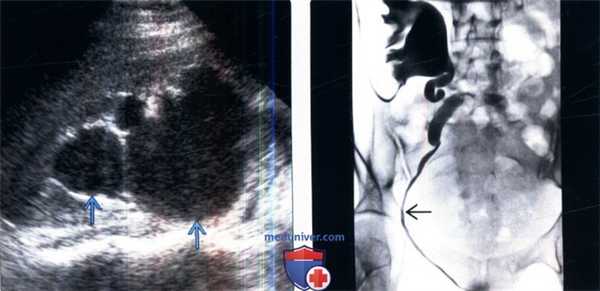

(Слева) УЗИ правой почки в продольной плоскости: у беременной женщины определяется необычное значительное расширение лоханки и чашечек справа.

(Справа) Антеградная пиелография, выполненная после родов у этой же пациентки: боковое смещение дистального отдела мочеточника справа увеличенной маткой. Обратите внимание на стойкое расширение проксимального отдела мочеточника и собирательную систему справа, несмотря на размещение катетера для нефростомии.